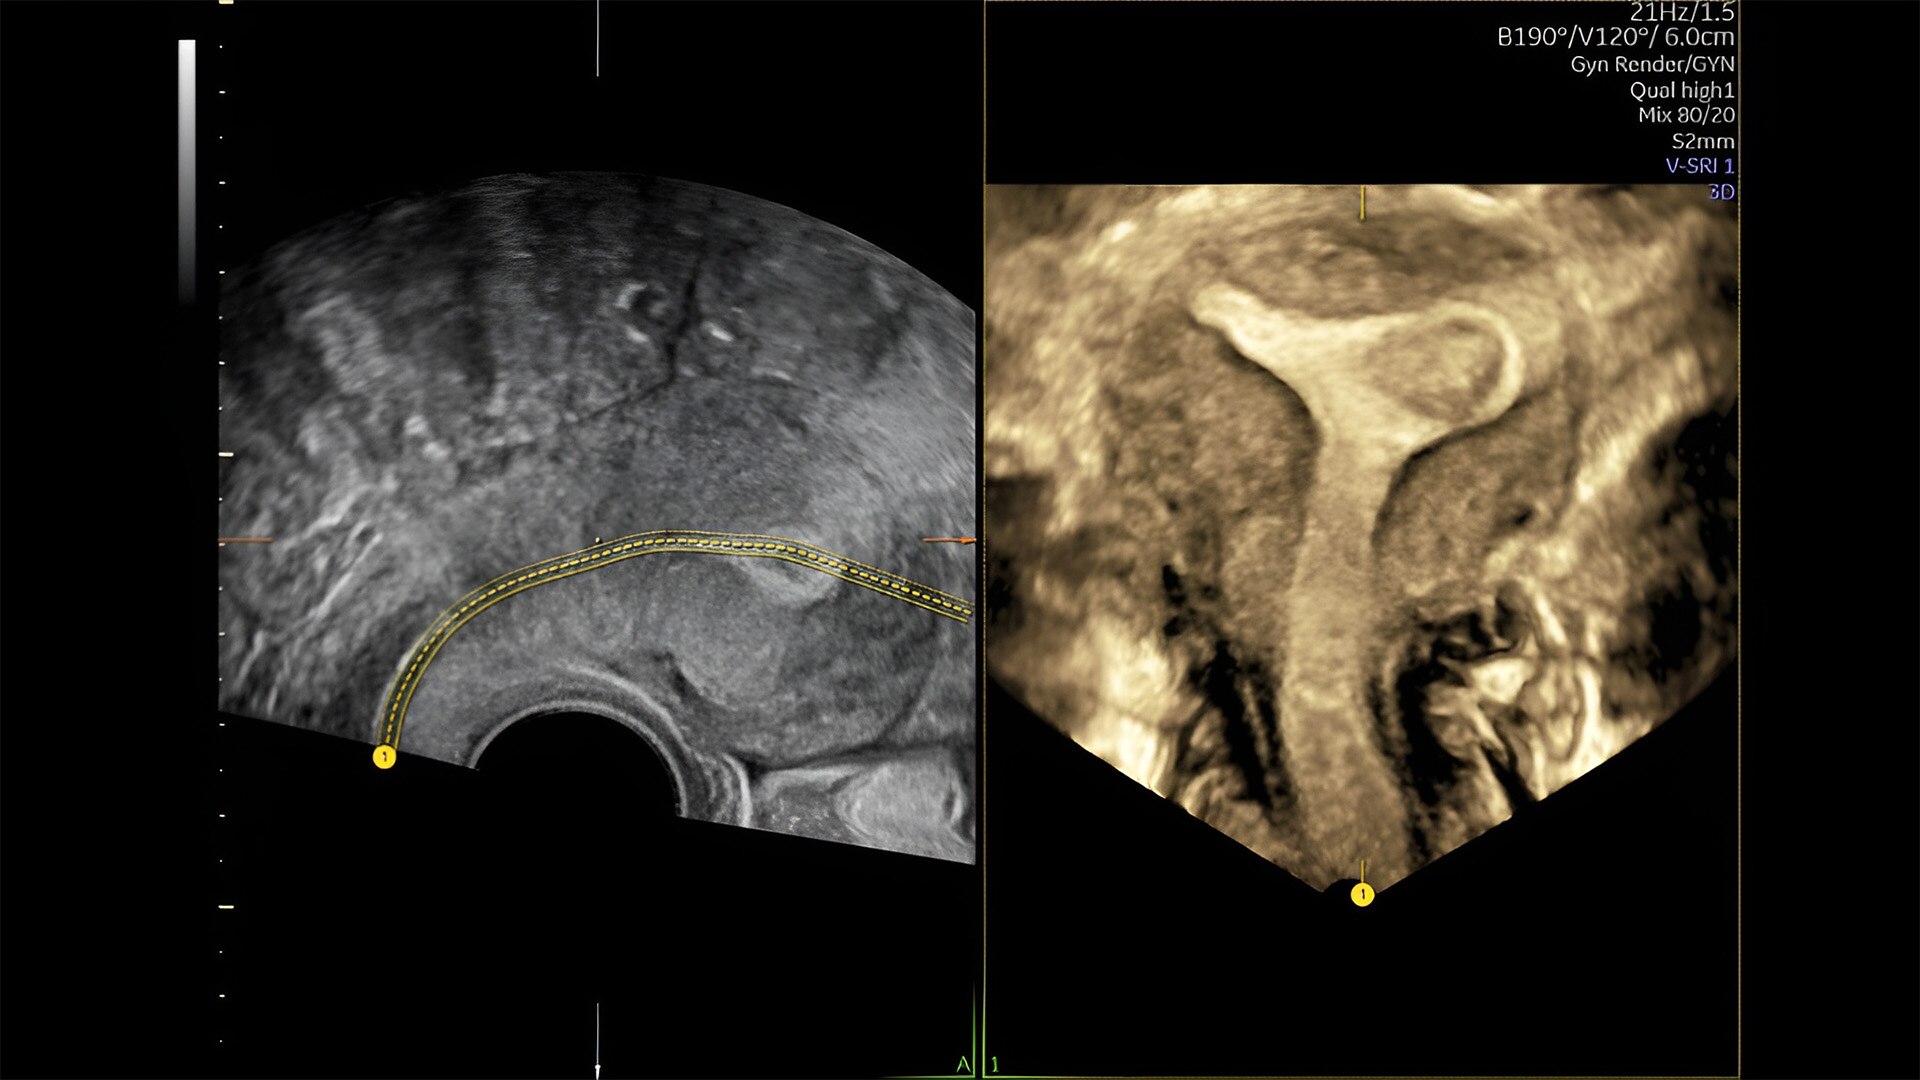

Pelvic health

Offer patient answers faster with Ai-based automation tools

Complex cases come with enough uncertainty. That's why the Voluson Expert 22 is specifically designed for in-depth assessment of complicated anatomy — with pioneering first trimester, fetal cardiac, gynecological, and other pivotal technologies that focus on early detection and intervention.